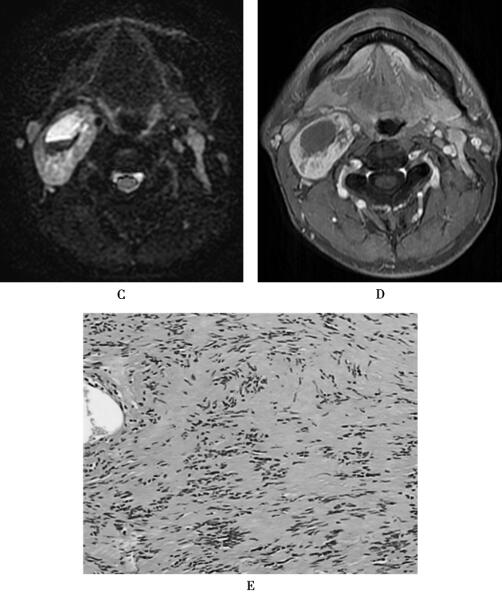

【最终诊断】

右侧颈动脉间隙神经鞘瘤。HE染色(×40倍),镜下可见梭形细胞栅栏样排列,细胞纤细(图1E)。

颈动脉间隙神经鞘瘤为起源于第9~12对脑神经施万细胞的良性肿瘤,常呈梭形或卵圆形,沿神经走行方向呈纵向生长。本病可累及任何年龄人群,以成年人多见,其临床病程较长,主要表现是颈外侧部肿块,边缘光滑,边界清楚。病理上肿瘤主要由Antoni A区和B区组成,前者细胞呈梭形,排列紧密,在T1WI呈等或低信号,T2WI为等或高信号,增强扫描病灶显著强化;后者细胞少,排列稀疏,呈网格样,细胞间有较多液体,位于肿瘤囊变区,在T1WI呈明显低信号,T2WI呈明显高信号,增强扫描无强化。因神经鞘瘤多来自迷走神经,通常将颈内静脉向后外侧推移,颈内动脉向前内侧推移,血管受压变窄。